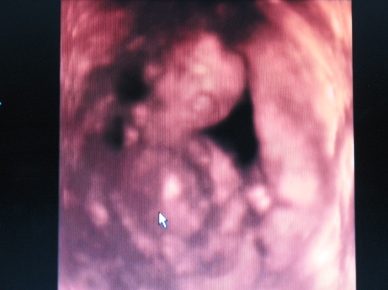

Ja én holnap megyek este uhra. Szombaton teszek fel képet, ha tudok.